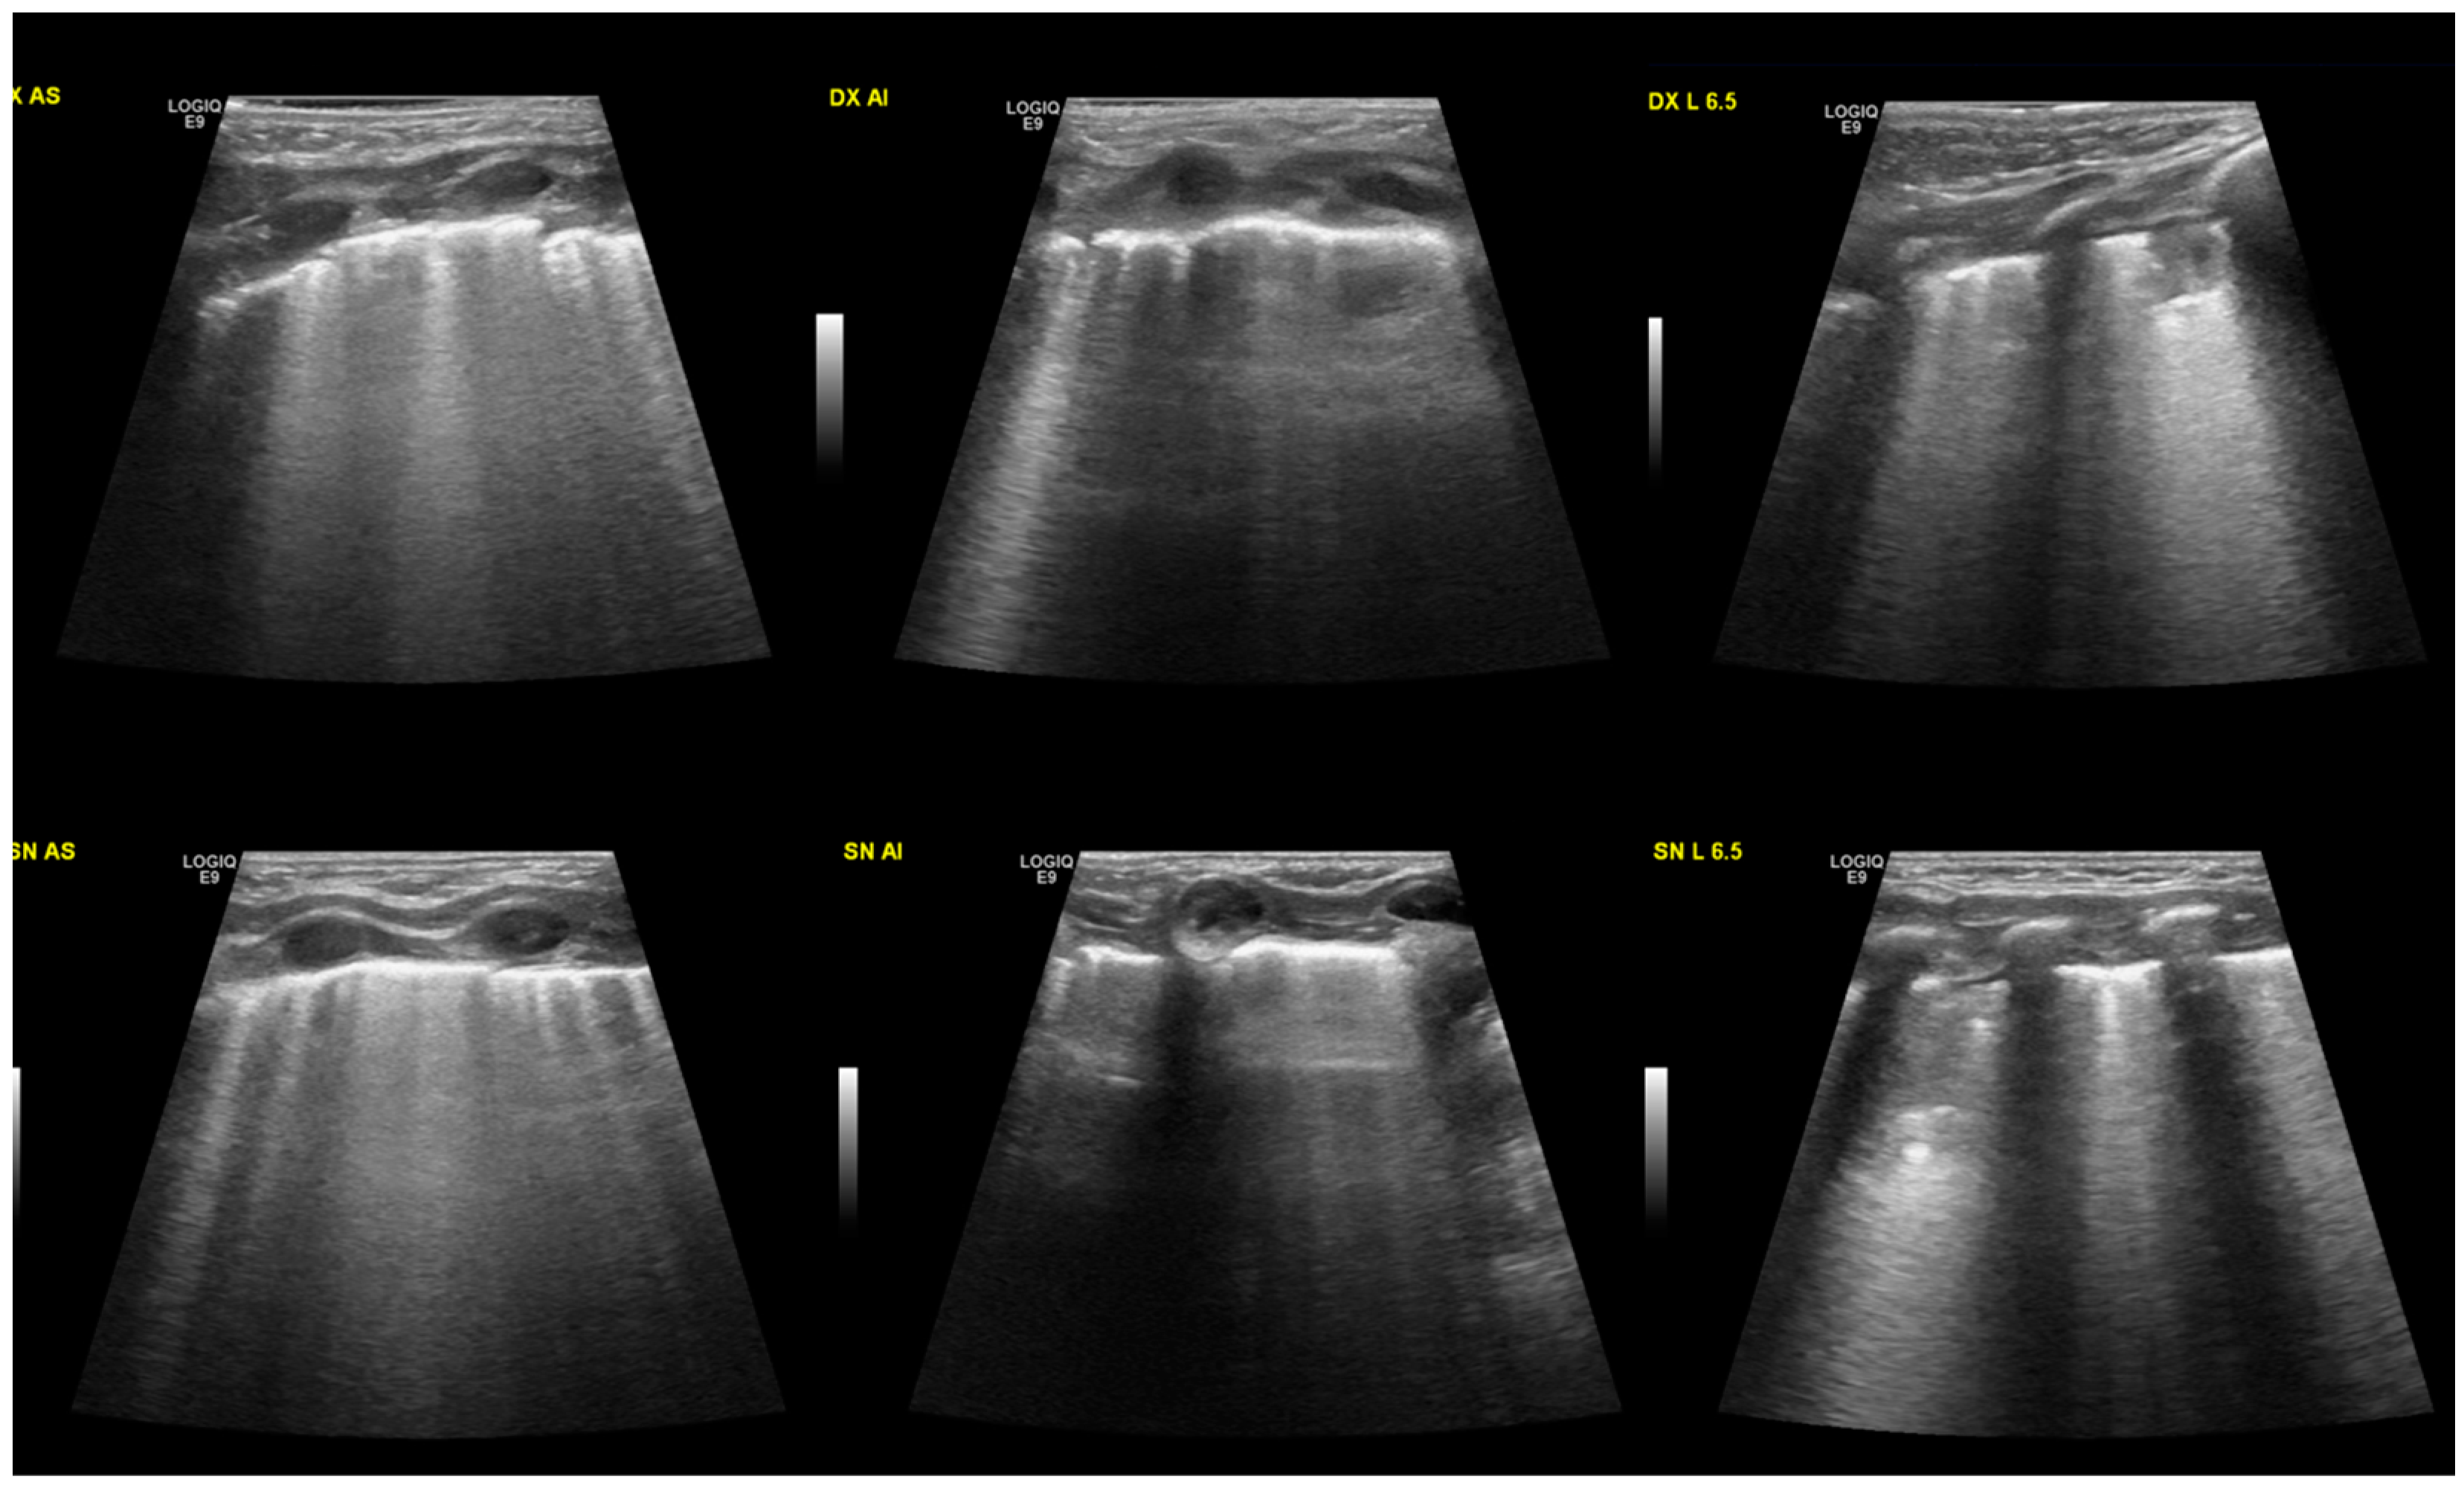

At the lung ultrasound performed in the first 6 h of life, all the neonates presented the same characteristics, with alveolar-interstitial syndrome shown by a diffuse B-line, often coalescing. All the neonates observed also presented pleural line anomalies such as thickening and interruption (Figure 1). In all the cases, we observed the disappearance of A-lines in the involved areas. Lastly, all of them had subpleural consolidations with irregular shapes, variable sizes, and air bronchograms.

Figure 1.

Typical ultrasound findings in MAS: B lines, often coalescing, and the pleural line is thickened and interrupted. Small consolidations (less than 1 cm) can be found in different areas of the lungs. At the top of the image, the right lung is shown, divided into three areas: the upper anterior, lower anterior, and lateral. In the lower portion of the image, the left lung.